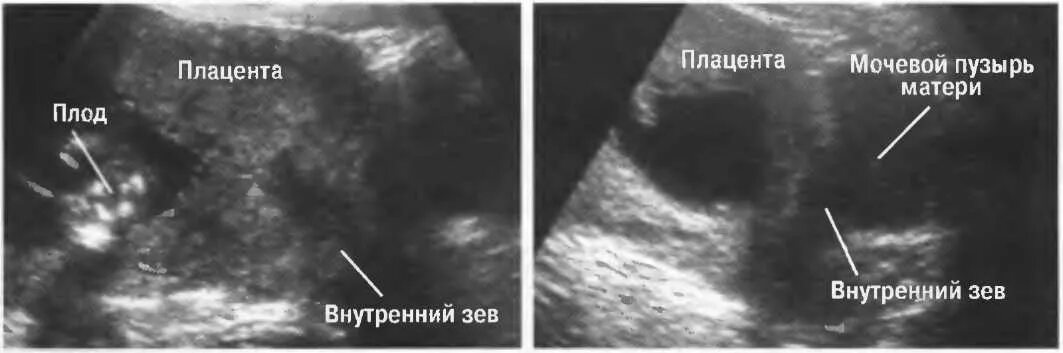

Тонус передней стенки матки